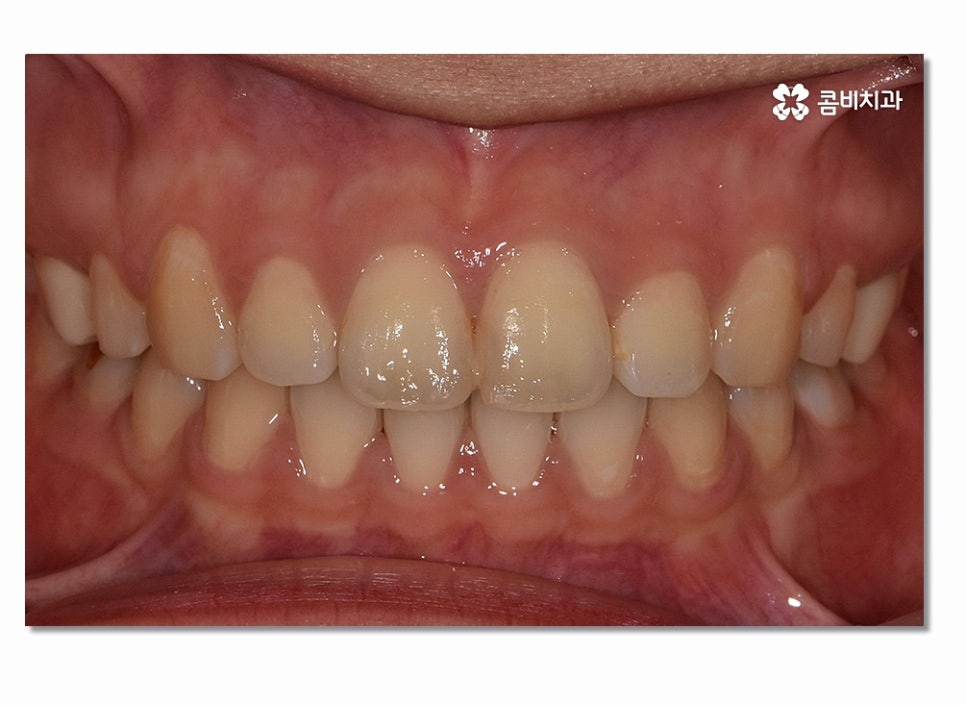

위 사진을 보시면 치아교정 과정을 통해서 치열의 가지런함은 물론이며

측면에서 보더라도 돌출입이 많이 개선된 것을 느낄 수 있을 거예요.

돌출입치아교정이 시작되면 이처럼 전방으로 뻐드러진

앞니를 시간이 지남에 따라서 후방으로 이동시키면서 돌출입이

점점 개선되며 이러한 치열의 변화는 교합도 잘 맞물리도록